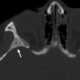

Lucent bone lesion with sclerotic rim

May Be Caused by